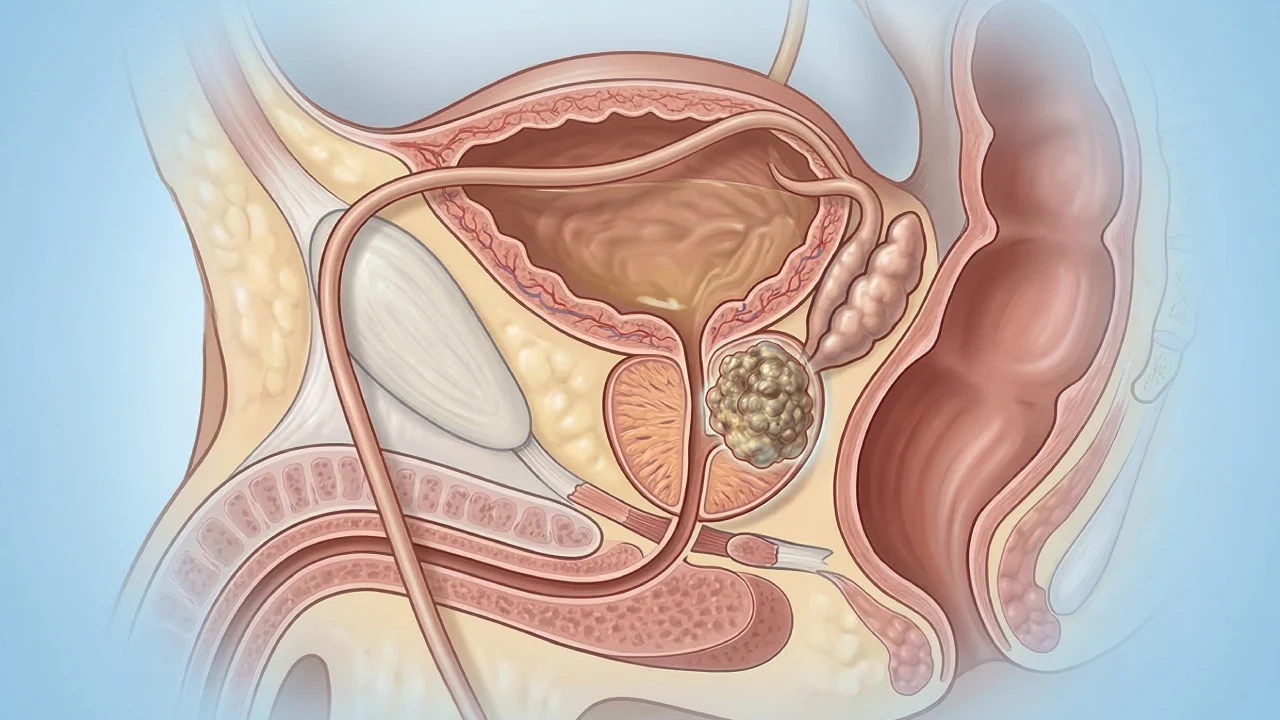

Prostate Cancer

Prostate cancer occurs when abnormal cells grow in the prostate gland.

Testicular Cancer

Testicular cancer develops in the testicles and needs early diagnosis.